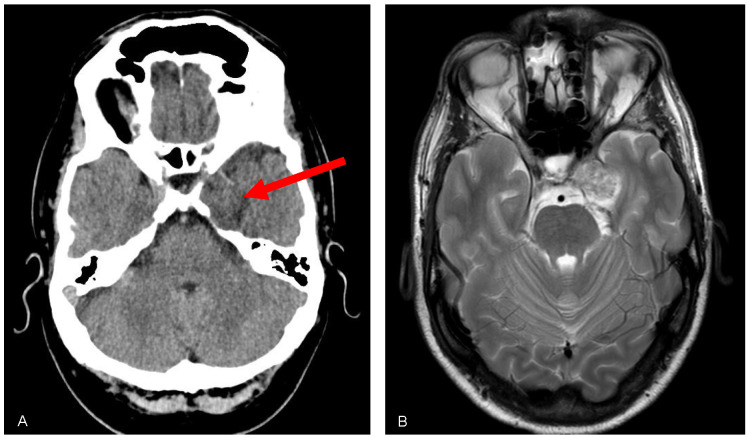

Meckel's cave tumour, a rare benign tumour originating from the Schwann cells surrounding the trigeminal nerve within the Meckel's cave region, can present with a variety of clinical manifestations. We report a case of a 44-year-old male patient who presented with symptoms of tear deficiency, including dryness, ocular discomfort, and blurred vision. Diagnostic evaluation revealed the presence of a Meckel's cave tumour harming the trigeminal nerve, leading to alacrimia. This case highlights the association between Meckel's cave tumour and tear deficiency disorders.